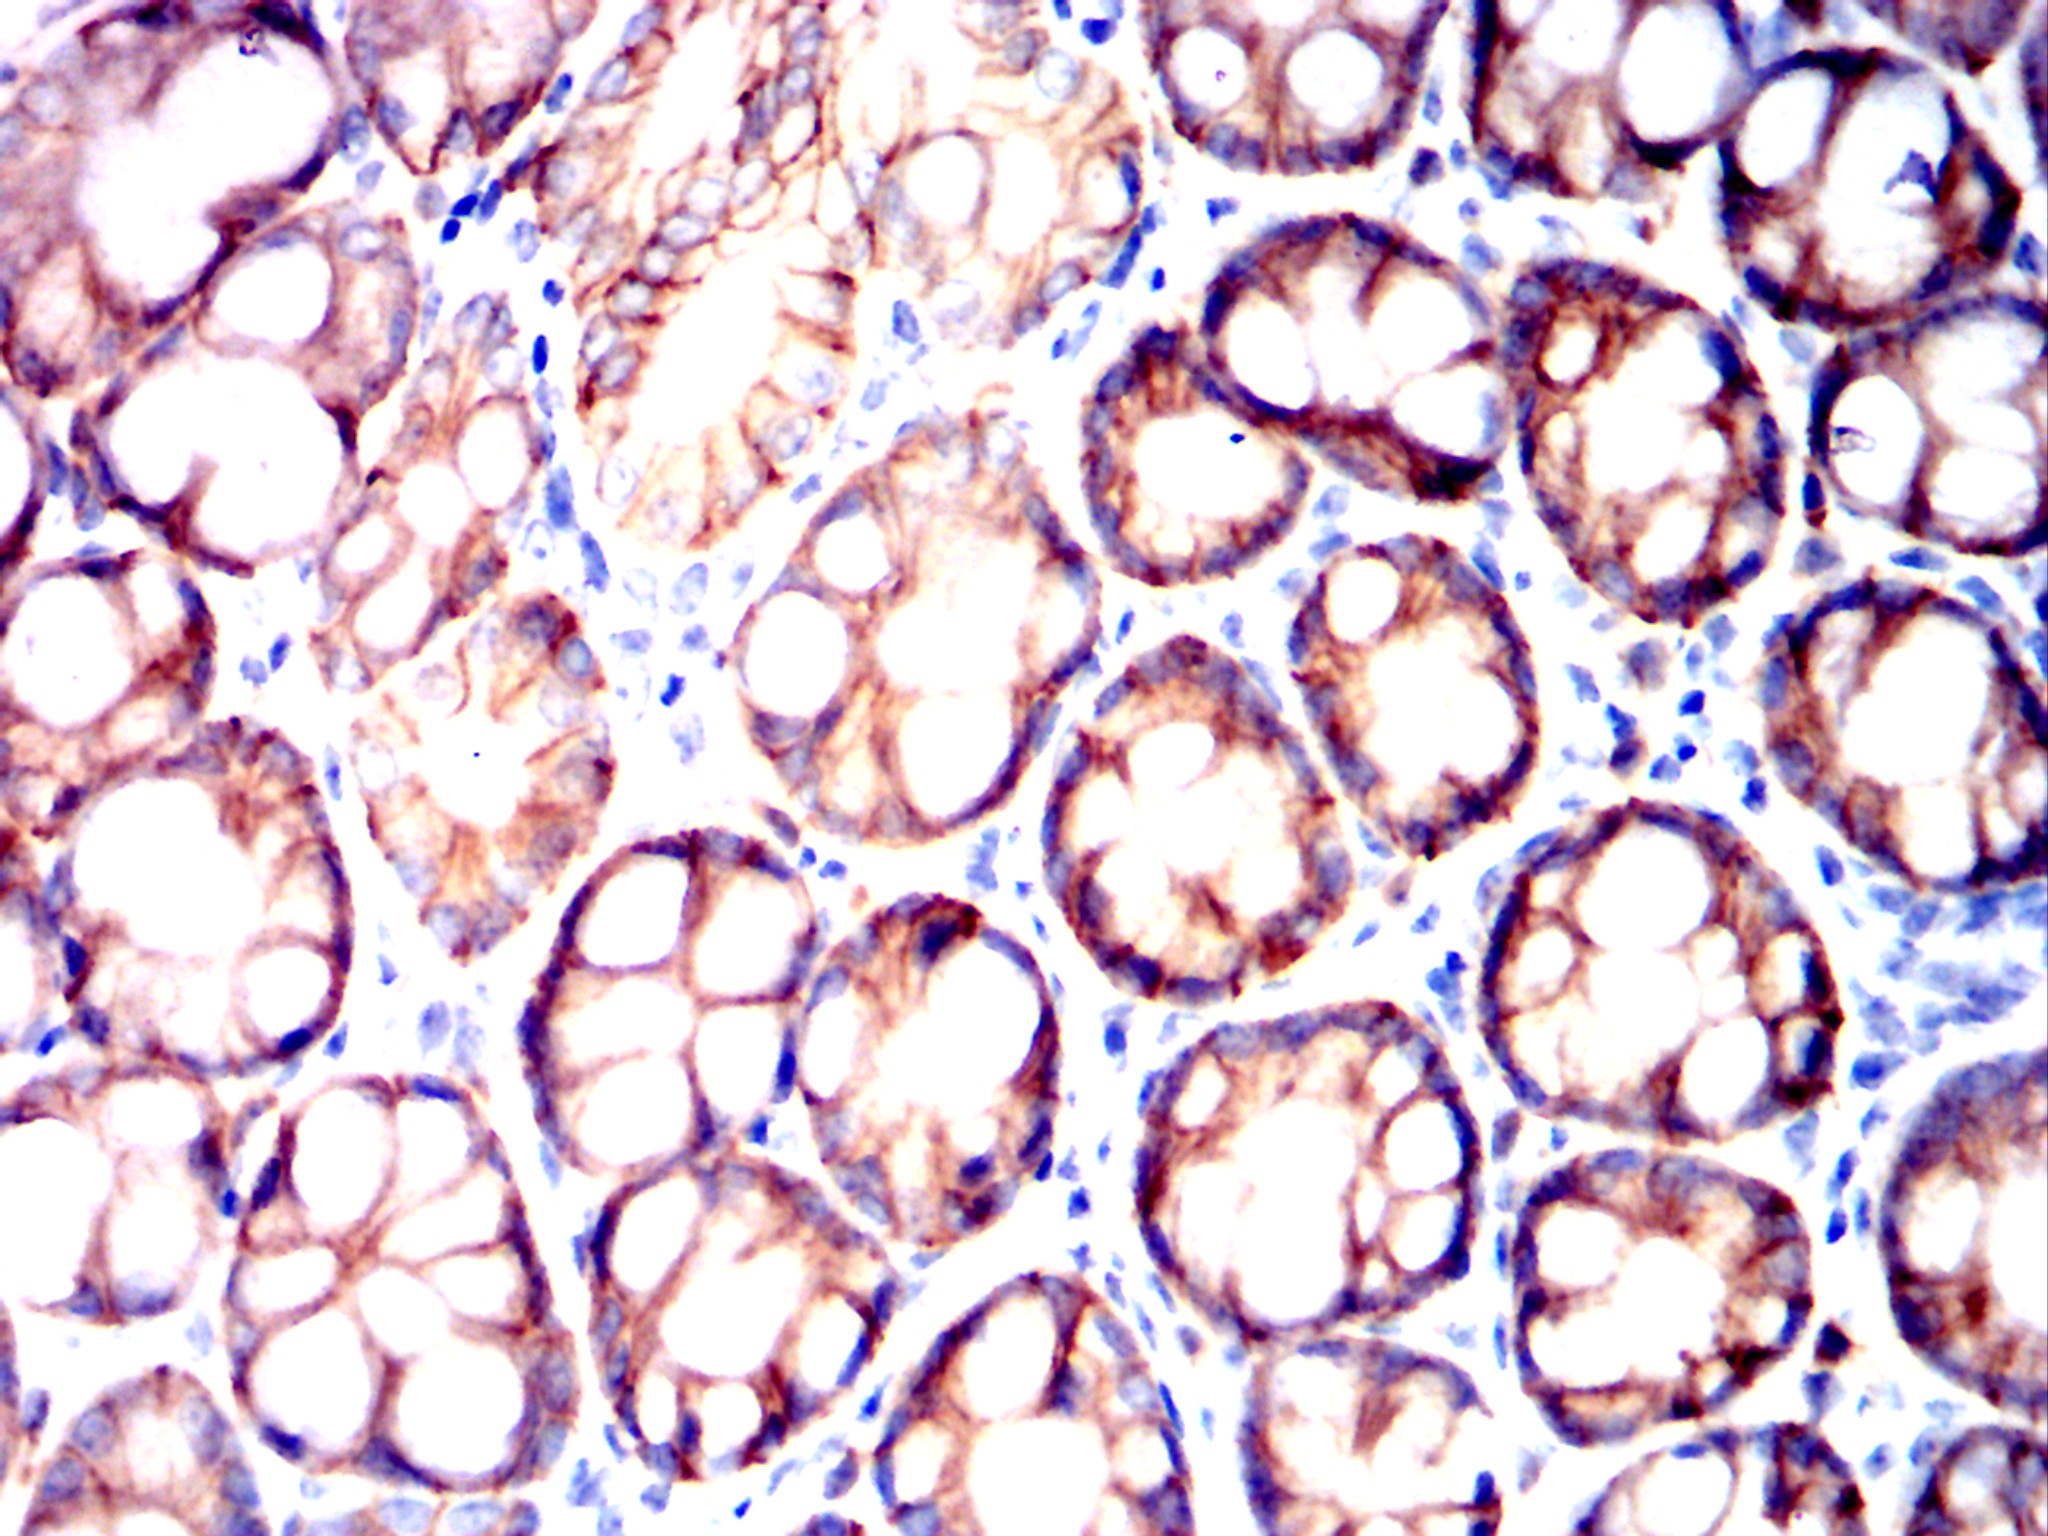

Immunohistochemical analysis of paraffin-embedded Mouse colon using EPCAM mouse mAb with DAB staining.